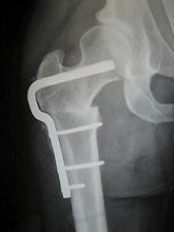

My job was initially predominantly orthopaedics, which I enjoyed as I had a pleasant and up-to-date boss, a New Zealander, John Addison. He had me doing the latest you-beaut procedure in no time – the Austin Moore prosthesis – for fractured necks of femurs.

McMurray osteotomy L and Austin Moore prosthesis R

John had developed his own technique for this and had his anaesthetist photograph the whole procedure on super-8 film so he could show it at orthopaedic meetings. The Charnley hip procedure was just coming into vogue and he was about to swing over but in the meantime he had me doing a McMurray osteotomy for osteoarthritis of the hip, a procedure which did not have a very long shelf life. It was designed to alter the weight-bearing of an OA hip and thereby relieve pain.

The policy on the unit for the numerous fractured hips we saw was to go directly to a replacement prosthesis for a subcapital fracture, rather than a Smith Peterson pin, which more often than not resulted in necrosis of the head of the femur, necessitating a second operation in a frail patient. I probably did 25 to 30 Austin Moores and that stood me in good stead at The Queen Elizabeth Hospital as a senior registrar later.